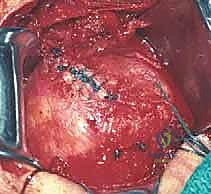

في حالات التمزقات الضخمة، قد تكون الأوتار متراجعة وملاصقة للعظم ومغطاة بالتليفات. هنا تبرز أهمية الجراحة المفتوحة، حيث يتم تحرير الأوتار بعناية فائقة وإعادتها إلى مرونتها الطبيعية لتصل إلى مكان تثبيتها الأصلي دون شد مفرط.

المرحلة الثالثة: زراعة الخطاطيف وخياطة الأوتار

يتم تحضير "بصمة الوتر" (Footprint) على رأس عظم العضد عن طريق تقشير العظم بلطف لتعزيز النزيف الخفيف الذي يجلب الخلايا الجذعية وعوامل النمو لتسريع التئام الوتر بالعظم.